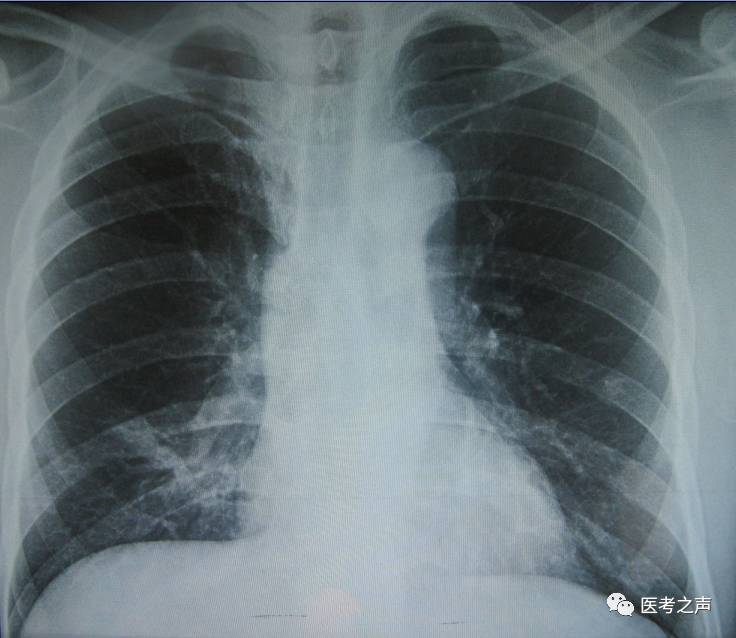

X线

像把面包压扁了看

X光是穿透性很强的射线,能够穿透人体,使用X线对人体内部进行透视或摄影的检查方法,其原理是利用了X线的穿透作用。在穿透人体时,被含钙的成分(骨)、水分(血液等)、软组织(肌肉)等吸收而减弱,X线会穿过人体,遇到被遮挡的部位,底片上不会曝光,洗片后这个部位就是白色的。因此可以呈现出所检查部位的基本形态。

就像一片面包或一块棉花,看不到里面的纤维纹理,但用手压瘪了会清晰一些。X线最大缺点是受制于深浅组织的影像相互重叠和隐藏,有时需要多次多角度拍摄X线片。

1、胸部和骨科检查用X线或CT

胸部X线可以检查心、肺、纵隔以及肋骨、胸膜、主动脉,比如肺纹理增多、肺部钙化点、主动脉结钙化等。

相比X线,胸部CT检查显示出的结构清晰度更明显,对胸部病变的检出敏感性和显示病变的准确性均优于常规X线胸片。胸部CT检查有利于检出轻微病变和隐蔽部位病变,显示病变特征,特别是对于早期肺癌的确诊有决定性意义。然而,CT检查的辐射剂量显著高于X线。